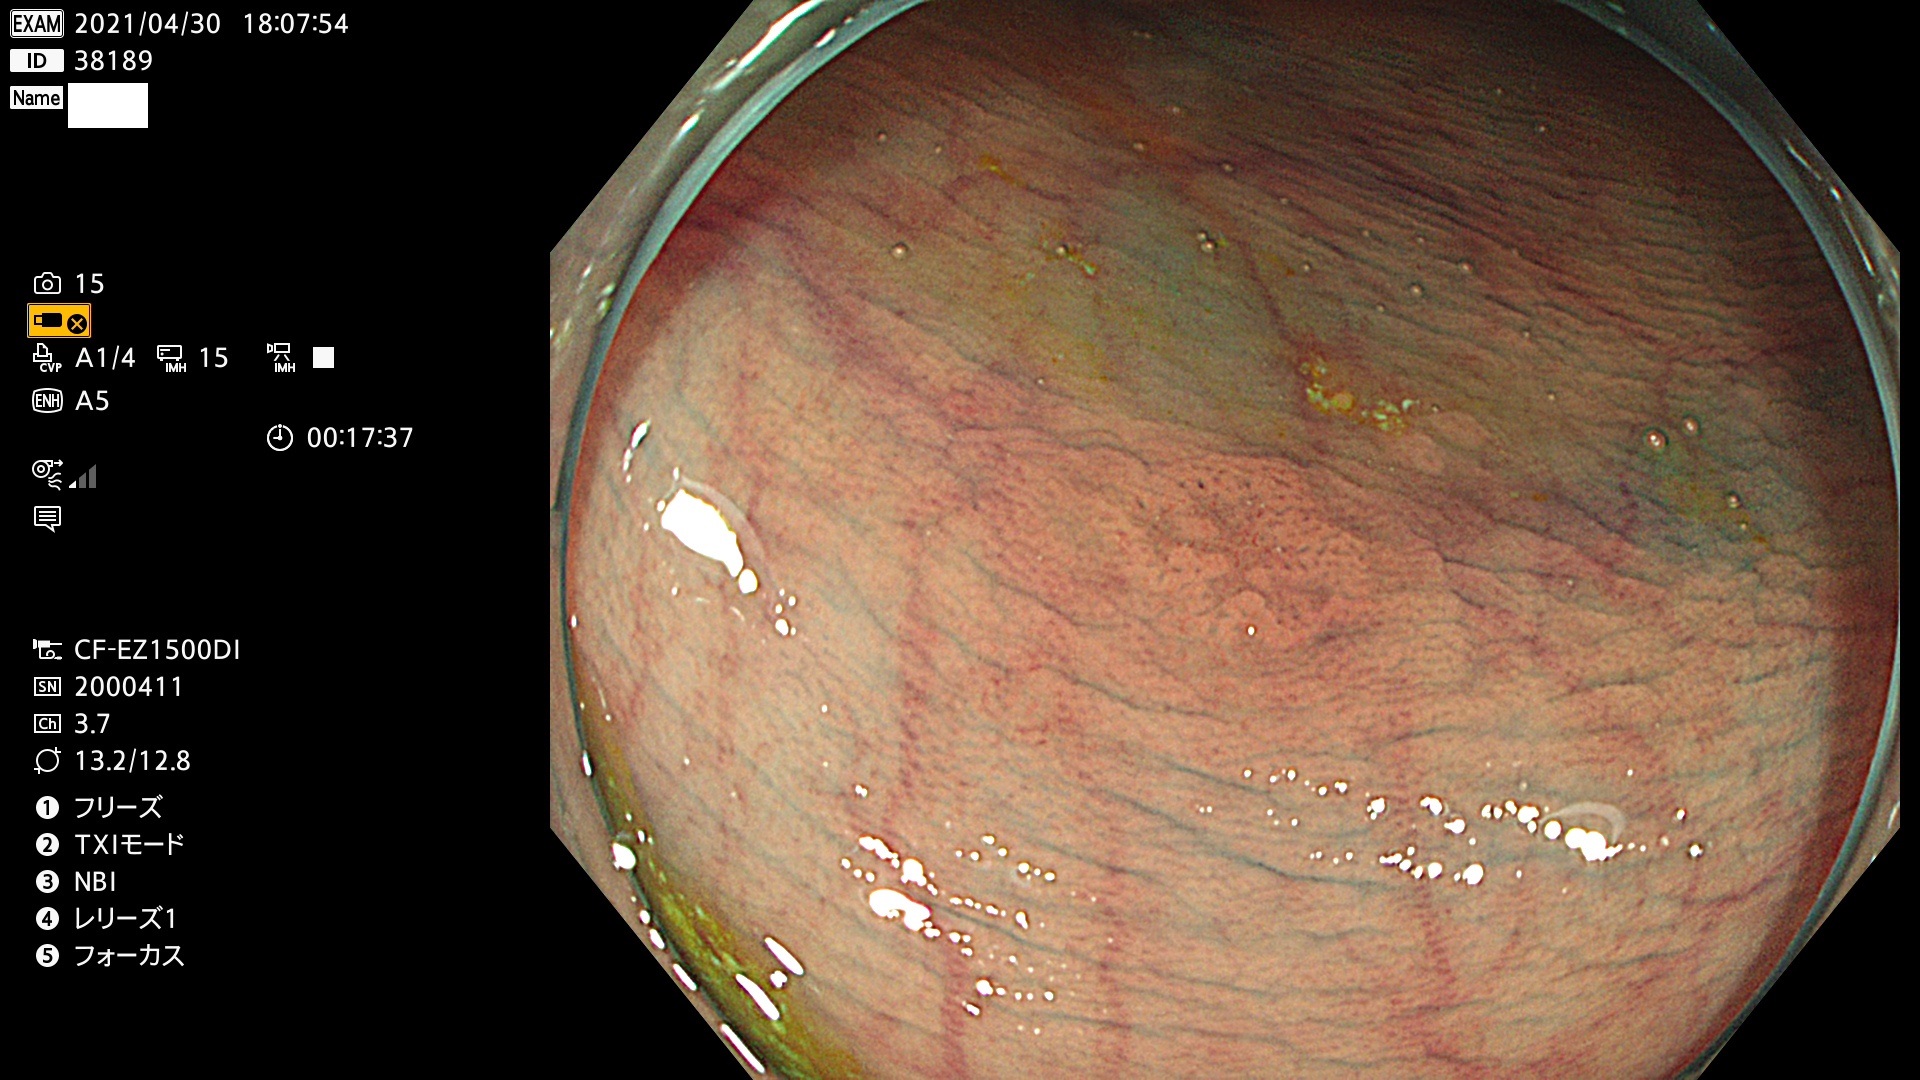

腺腫発見率 72 % (カルテ番号 38100〜38199の100名の方の検査結果で集計)大腸癌検診最新情報

以下のカルテ番号の方に腺腫(Adenoma,Group3〜5)が見つかりました(集計法)

38101 38103 38104 38106 38107 38108 38109 38110 38111 38112 38113 38114 38115 38117 38118 38122 38123 38124 38125 38126 38127 38128 38130 38131 38132 38135 38137 38138 38140 38141 38142(SSAPのみ) 38143 38144 38145 38146 38147 38148 38149 38150 38151 38152 38153 38154 38157 38158 38160 38161 38162 38164 38165 38166 38167 38168 38169 38172 38176 38177 38178 38181 38182 38183 38184 38187 38189 38190 38191 38192 38193 38194 38195 38196(SSAPのみ) 38198

発見困難で危険性の高い平坦型病変(上記100名より抽出) ![]()